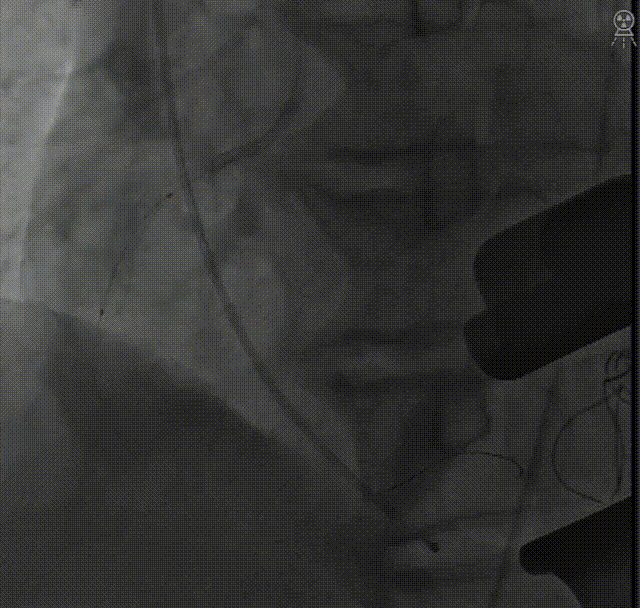

穿刺心尖,导丝跨瓣:

主动脉根部造影:

定位件入窦后造影:

降瓣至窦部:

完成瓣膜释放:

复查根部造影,未见明显反流:

台上复查食道超声,瓣架圆形展开,启闭良好: